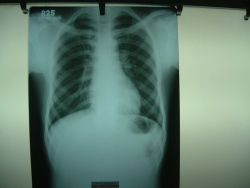

Where are X-rays useful?

X-rays have been used to look at all parts of the body.

Specifically, they are required for the chest, all bones and joints and

for the abdomen.

Are there any newer advances in X-rays?

X-rays are used in CT scanning (computed tomography). Digital

radiography uses X-rays for directly producing images on a computer,

bypassing the film - this is very helpful in emergency situations,

such as the trauma centre or intensive care unit.